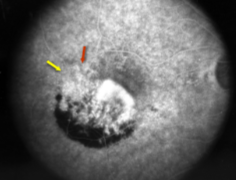

classic & occult CNV

type 2 MNV

MNV type 2

MNV type 2

MNV type 2

MNV type 2

MNV type 2

type 1 MNV

fibrovascular PED

late leakage from undetermined source (poorly defined neovascularization)

speckled hyperfluorescence

dye pooling late in study

poorly defined